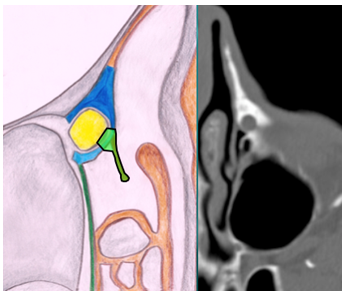

During the surgical procedure the use of a rigid light probe inserted in the inferior lacrimal punctum and canaliculus allows identifying the projection of the lacrimal sac on the lateral nasal wall (Figure 1). In fact, the site of major illumination helps the operator in defining where the bone is thinnest in the lacrimal fossa. This technique further confirms the relation between UP and lacrimal bone, already evaluated with CT. As shown in Figure 2, the prelacrimal UP hides the lacrimal bone making its removal necessary in order to realize the ostomy with the lacrimal sac.

Figure 1 Left nostril – transillumination of the lacrimal sac.